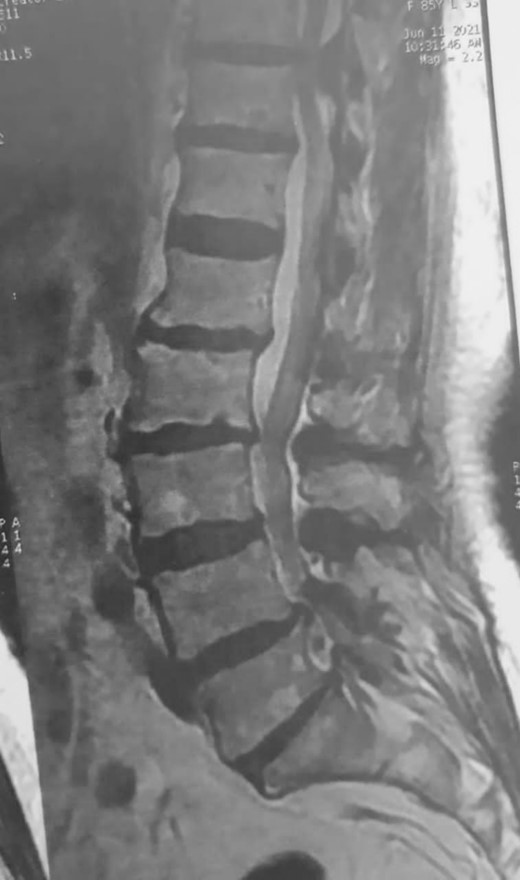

An otherwise healthy 80-year-old female patient presented with left lower extremity weakness following frequent falls ~1 month ago. Upon examination, motor power in the left lower limb was graded as III, accompanied by hypoesthesia. Without any other accompanying symptoms, magnetic resonance imaging (MRI) of the spine revealed a lesion within the vertebral canal causing compression of the spinal cord at the D10–D11 level (Fig. 1). T1-weighted images (T1WI) displayed hypointense calcified regions

Preoperative MRI, sagittal view, T2WI, shows tumor mass at levels D10–D11.

within the lesion, while T2-weighted images (T2WI) exhibited variable signal intensity, predominantly hypointense, in addition to surrounding tissue changes indicative of compression and edema (Fig. 2). Subsequently, the patient underwent surgical excision of the lesion, including laminectomy of D10–D11. A sharp dissection of the mass from the dura was performed during the surgery (Fig. 3). Two months after surgery, the patient underwent a short course of physiotherapy for several weeks, and now they can ambulate without support. The postoperative period was uneventful. Histopathological analysis revealed the presence of classical psammoma bodies, characterized by calcium deposits or punctate calcifications within the tumor mass, consistent with a diagnosis of classic meningioma ossified (Fig. 4). A follow-up MRI performed after 3 months demonstrated complete excision with no evidence of tumor recurrence (Fig. 5).